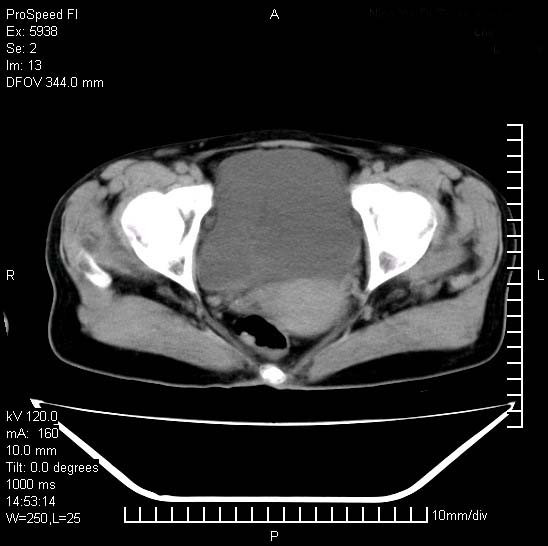

反复小腹疼痛,盆腔积液3年,无发热,曾抗痨一段时间。

右下腹肠管壁增厚,边缘有侵润改变及点状低密度影,内侧可见局限性肿块。考虑-----淋巴瘤或增生型肠结核----盆腔积液-----建议肠镜检查

结核性腹膜炎伴积液。右侧髂骨骨窗看看,是否有骨质破坏。

提示结核性腹膜炎合并盆腔积液。建议查ppd或tb抗体。

盆腔积液